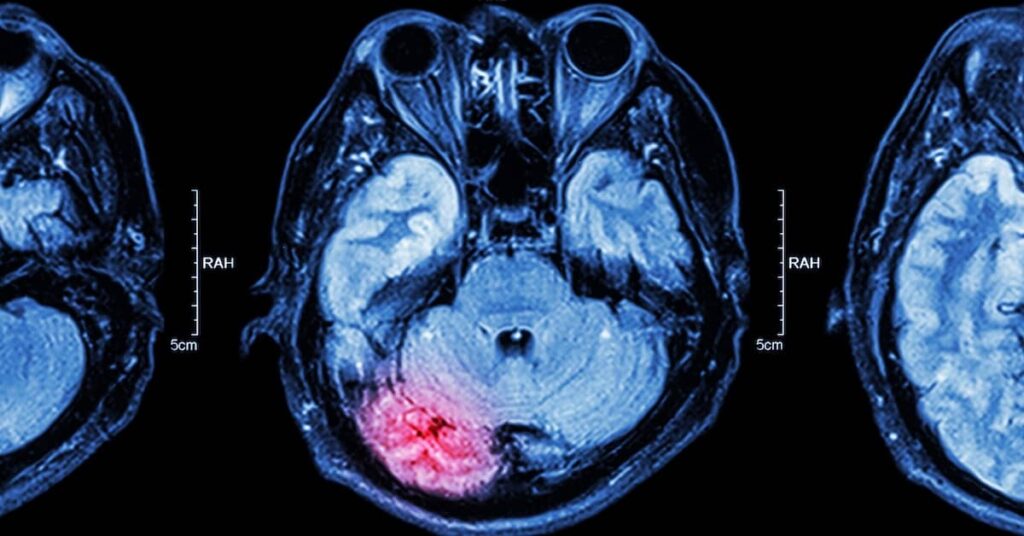

Milder brain injuries may not generate any of these symptoms and might require more extensive examination and analysis for diagnosis. A variety of imaging technologies, such as a CT scan or an MRI, can help diagnose the specifics of the brain injury.

Part of the reason is that closed head TBIs are difficult to “see” and prove because of the lack of visible, objective physical injuries that can be shown in court. Brain imaging (such as CT scans, MRIs, PET scans, and SPECT scans) can be useful for diagnosing and proving brain injury claims. Neuropsychological testing may be necessary or recommended for identifying cognitive difficulties and deficits.